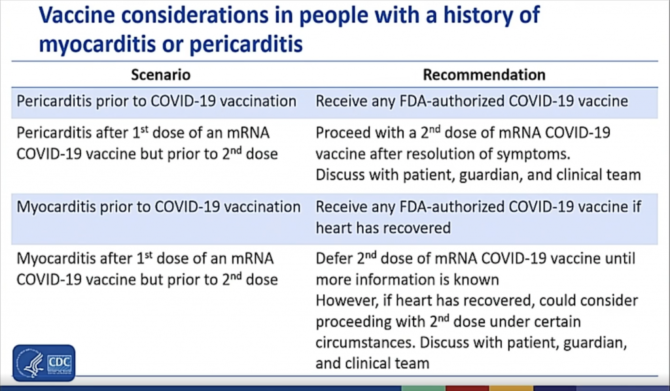

Durante la presentación, un portavoz de los CDC dijo que se actualizarán las consideraciones sobre la vacuna para las personas con antecedentes de miocarditis y pericarditis:

Se recomienda a las personas con antecedentes de pericarditis que reciban cualquier vacuna COVID autorizada por la FDA.

Se recomendará a cualquier persona con antecedentes de miocarditis que reciba una vacuna COVID autorizada por la FDA si su corazón se ha recuperado.

A las personas con antecedentes de miocarditis después de la primera dosis de una vacuna de ARNm se les animará a aplazar la segunda dosis hasta que se conozca más información, pero si el corazón se ha curado, podría considerarse una segunda dosis.